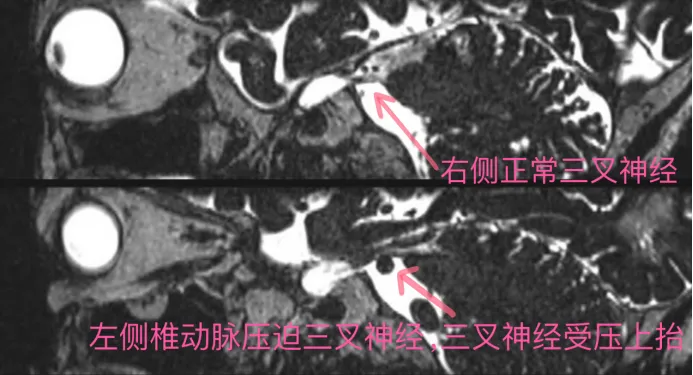

黄陂区人民医院放射影像科二区针对三叉神经痛开展的三叉神经磁共振检查,能获得高信噪比、高空间分辨率的图像,便于观察三叉神经与其邻近血管之间的关系,同时也能判断附近是否有肿瘤占位挤压,有助于明确三叉神经痛及面肌痉挛的病因,为临床治疗及手术提供诊断依据。